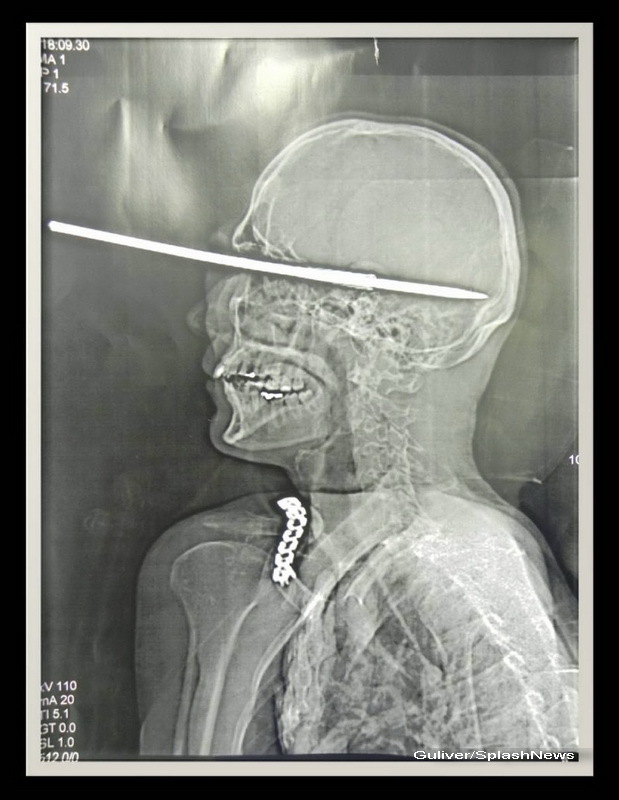

Barbatul a vrut sa curete arma cu harpon. Din greseala, a declansat-o, iar harponul i-a strapuns craniul si i-a intrat in creier. Ca prin minune, pescarul a supravietuit. Ba mai mult, creierul nu i-a fost afectat.

Barbatul era complet lucid cand a ajuns la spital, chiar daca harponul i-a strapuns ochiul stang si s-a oprit milimetric de artere importante.